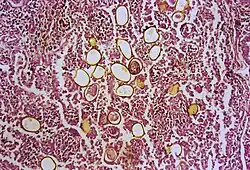

Le premier cas d'infection chez l'Homme a été observé en 1879 à Taïwan : une autopsie a retrouvé des vers trématodes adultes, de couleur brun-rouge, de forme ovoïde, dans les poumons du sujet. Les douves adultes sont dotées de deux ventouses : l'une à l'avant en partie supérieure, l'autre ventrale et au milieu du corps. Ces douves peuvent vivre 20 ans. Leurs œufs, asymétriques, sont de teinte brunâtre et dotés d'une membrane protectrice épaisse. Comme on l'a déjà dit, le cycle de vie de ces trématodes est complexe et ne comporte pas moins de sept phases, à travers des hôtes successifs jusqu'à l'homme[10] :

La paragonimose provoque une pneumonie aux symptômes caractéristiques : des toux prolongées, des douleurs thoraciques, une perte d'haleine et des crachements de sang[12]. En raison des différents symptômes, cette maladie est appelée indifféremment hémoptysie endémique, hémoptysie parasitaire, distomatose pulmonaire d'Extrême-Orient, ou parasitare haemopte. La forme pulmonaire est de loin la plus fréquente, avec 76–90% des cas d'infection. Les formes extra-pulmonaires sont dues à la migration des douves hors du système respiratoire. Par exemple, la paragonimiase cutanée, qui se caractérise par la présence de boutons instables, est fréquente chez les enfants[9]. La migration vers le cerveau est mortelle ; elle s'accompagne de céphalées, de troubles visuels et de handicaps moteurs[4].

La phase aiguë (contamination et migration) est ponctuée de divers symptômes, qui vont de la diarrhée, aux douleurs abdominales en passant par la fièvre, la toux, de l'urticaire, une hépatosplénomégalie, des anomalies pulmonaires, et de l'éosinophilie. La phase chronique comporte des symptômes respiratoires comme la toux, le crachat de mucus incolore contenant des amas d'œufs[7], une hémoptysie, et des anomalies radiographiques. Des symptômes beaucoup plus graves apparaissent en cas de migration des douves hors des poumons, particulièrement lorsque le cerveau est touché[13]. Le diagnostic se fonde sur l'observation d’œufs dans le mucus ou les selles au microscope, mais il faut 2 ou 3 mois après l'infection pour que les œufs existent.